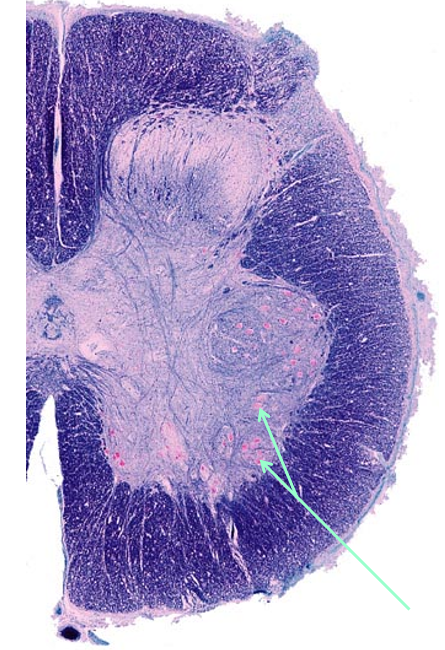

Poliomyelitis